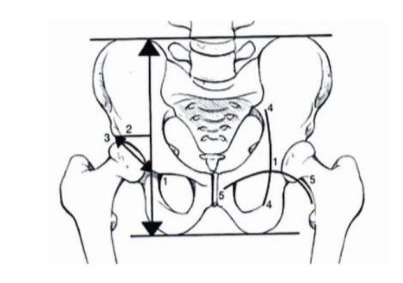

The Ranawat criteria remain valid for the use of Ranawat’s rules for preoperative planning [8]. The Ranawat triangle - the horizontal line between the iliac ridges, the horizontal line between the ischiatic tuberosities, and the perpendicular to these lines, by 5 mm lateral of the Kohler and Shenton lines. On this perpendicular, the acetabular height (of the radiological “U”) is 1/5 of the height of the pelvis measured; the depth of the cotyl is equal to the height. The hypotenuse of the Ranawat triangle unites the ends of the cathetes, and the center of rotation is in the middle of the hypotenuse Figure 2.

Figure 2: Ranawat’s rules for preoperative planning.

The Pierchon index for the correction of the femoral offset and the center of the hip rotation. For the dysplastic acetabulum, it is necessary to medialize and lower the center of rotation, and it is necessary to ensure good acetabular coverage [9].